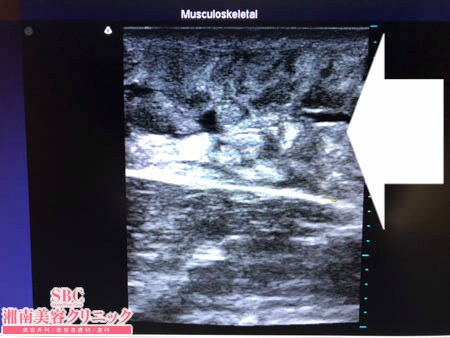

No.205018【脂肪吸引】【動画あり】湘南美容外科脂肪吸引最高責任者である竹田先生による脂肪吸引のフォトギャラリー!スタッフさんからの脂肪吸引のご依頼は何よりも信頼の証!二の腕全周の術中3Dタッチビュー・左二の腕

画像の通り。

しっかりと根こそがせてもらいました!